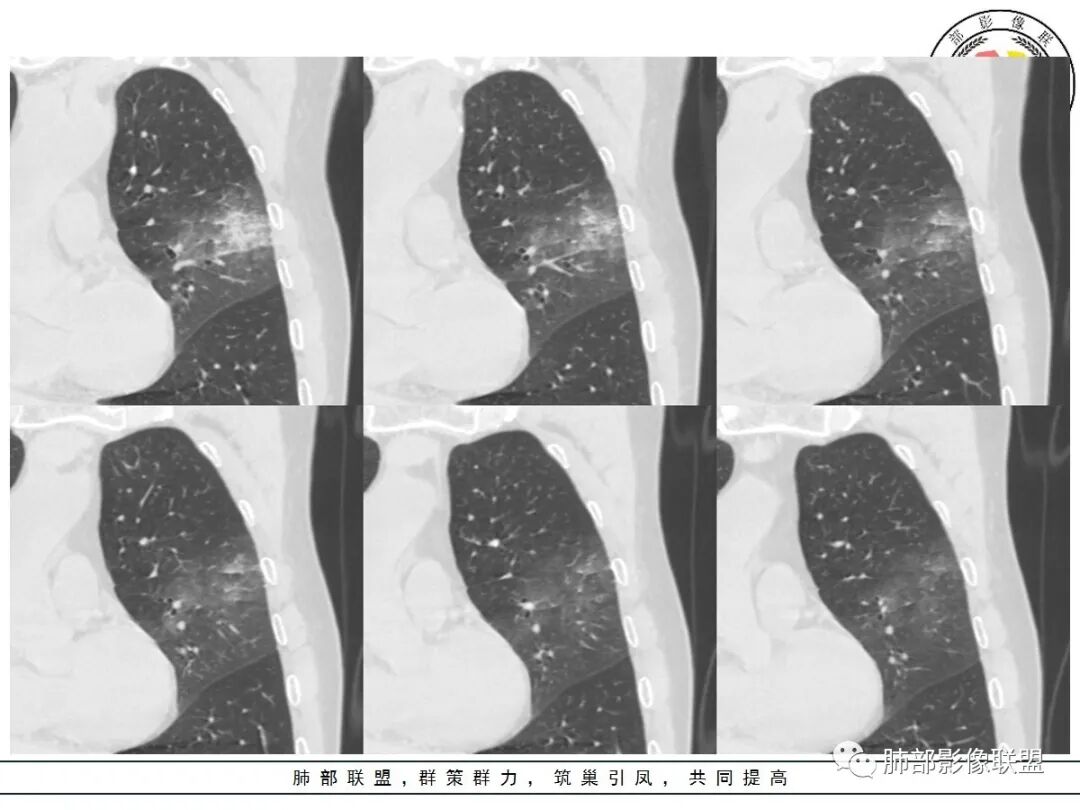

左肺上叶类圆形软组织影,边界较清楚,其内密度均匀,外侧缘可见空气新月征,并可见点状钙化,增强扫描可见均匀强化,病灶周围可见磨玻璃渗出性密度影,斜裂侧光滑平整。考虑炎性病灶,以肉芽肿性炎症为主(如真菌性肉芽肿),鉴别结核(无卫星灶,无多态性),肺癌(无毛刺,分叶等恶性征象,)细菌性炎症(密度一般不这么致密,很少钙化及空气新月征)。

左肺上叶类圆形软组织影,界清,内见空洞影,病灶周围斑片影,可见空气支气管征,未垮叶。考虑炎性病变,糖尿病四大金刚,肺克?毛霉?

老年男性,血糖升高六年,反复咳痰咳嗽3周,左肺上叶近斜裂类圆形肿块影,边缘伴磨玻璃影,边界不清。内部可见支气管走行、钙化、小空洞,叶间裂局部膨隆,增强扫描轻度强化,内部可见小的低密度区,边界尚清。考虑为炎性病变可能性大。

左肺叶裂旁实变影,宽基底与叶裂胸膜相连,边缘平直,部分略膨隆,病灶近段及上段支气管深入病灶内,部分壁略增厚,远端支气管截断,似有小空泡,壁规则,内部可见高密度钙化,周围可见模糊的GGO,血象正常,考虑结核(NTM),鉴别隐球菌,奴卡,放线菌。

老年男性,66,反复咳嗽、咳痰3月。糖尿病,血象不高。

胸部CT:左肺上叶类圆形肿块影,边界较清楚,密度较均匀,内可见小片坏死、偏心空洞、空气新月征、点状钙化,周围晕、絮状渗出、边缘模糊,支气管扩张、充气征、支气管进入病灶堵塞,叶裂牵拉明显,增强扫描中度均匀强化,纵隔可见淋巴结。考虑:炎性病灶,肉芽肿性炎症,曲霉?毛霉?鉴别:TB,淋巴瘤。

左上肺类圆形肿块影,边界较清楚,支气管通畅略扩张,周围磨玻璃影,其内密度均匀,外侧见空气新月征,且见点状钙化。叶间裂光滑稍膨隆。老年男性,糖尿病,高血压,痰培养克雷伯菌。综合考虑炎性病灶,克雷伯合并真菌感染,曲霉。结核合并真菌。鉴别肺癌合并感染。

左肺上叶类圆形软组织影,边界稍模糊,其内密度均匀,外侧缘可见空气新月征,并可见点状钙化,增强扫描渐进性强化,病灶周围可见磨玻璃影,斜裂侧光滑平整,气管未见明显闭塞,淋巴结未见肿大,糖尿病患者,首先考虑感染性变,结核并曲霉?

我标示一下,尖后段搭到一部分,前段也占了一点点。

主体在舌段